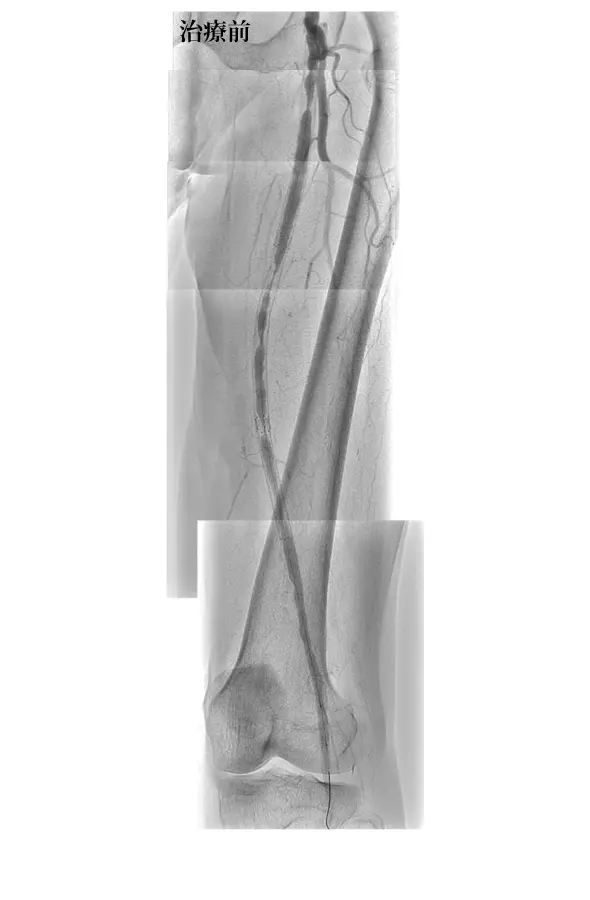

ターボタンデムの症例(下肢)